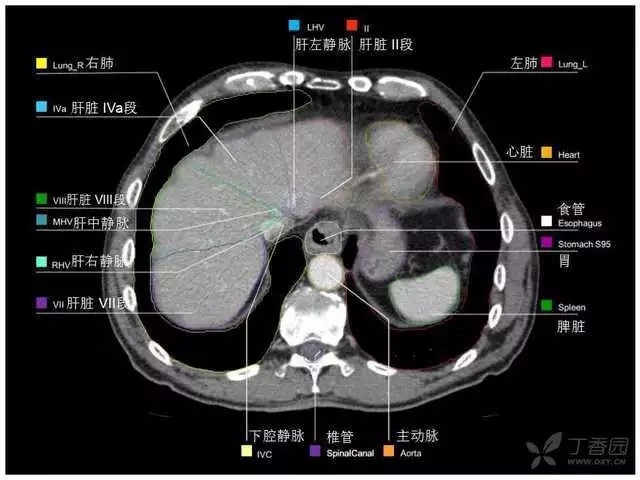

腹部肝脏高清CT断层的图谱

全腹部高清CT图谱,淋巴结彩色图谱,血管解剖图谱大汇总!

超声肝脏分叶及分段

肝脏分段和基本解剖学标志